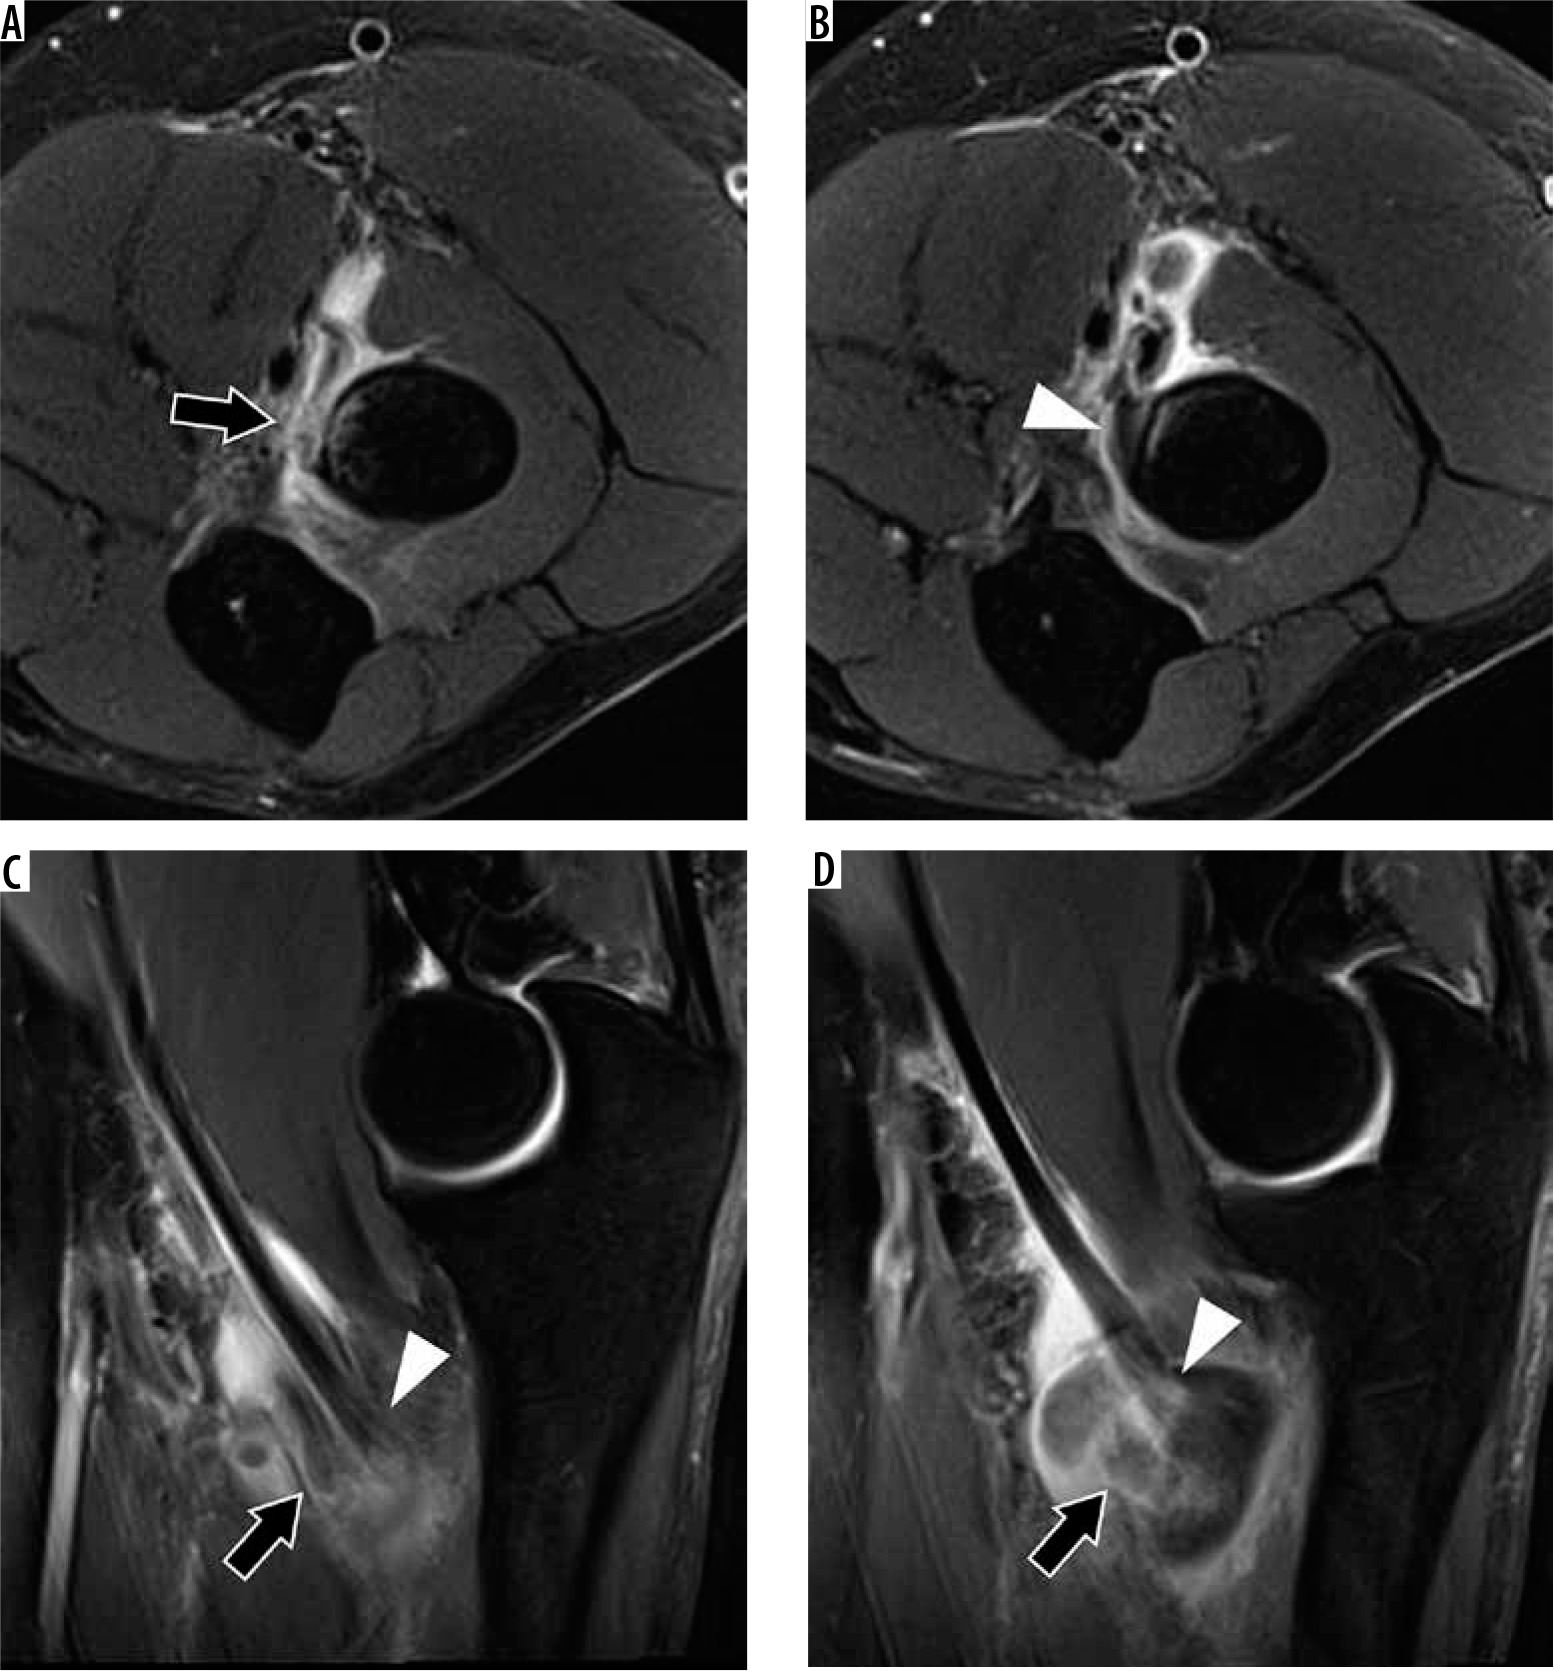

Figure 18

30-year-old man with elbow dislocation after a fall. A) Sagittal oblique and (B) axial proton density-weighted fat-suppressed magnetic resonance imaging shows a non-displaced fracture of the anteromedial facet of the coronoid process (arrows), consistent with posteromedial rotatory instability. Also present is a joint effusion (arrowhead in A) with periarticular soft tissue oedema